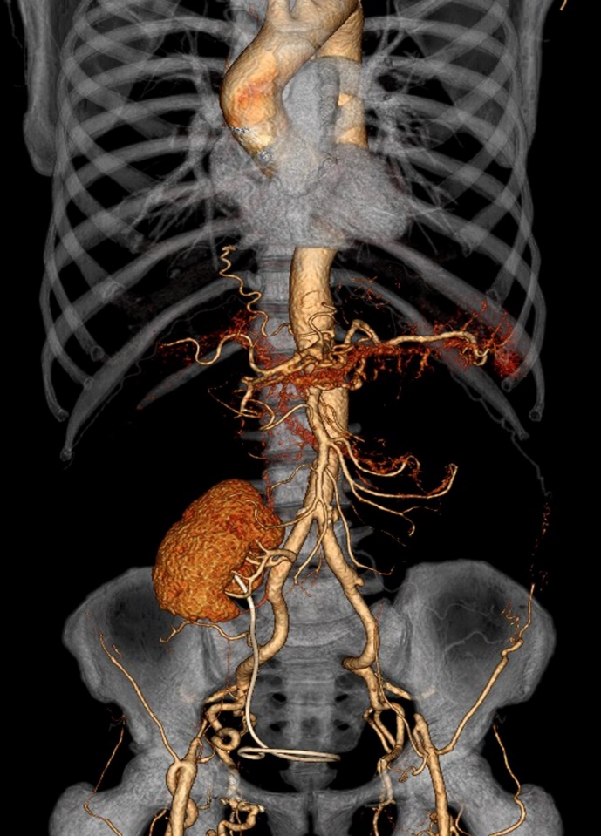

男性,38岁,双侧复杂性肾动脉瘤

03

肾周型腹主动脉瘤(瘤体累及双侧肾动脉)

男性,46岁

瘤体起于肠系膜上动脉开口下方,双侧肾动脉开口于瘤体

拟行双肾自体移植:右肾血管严重变异,无法重建,仅行左肾移植